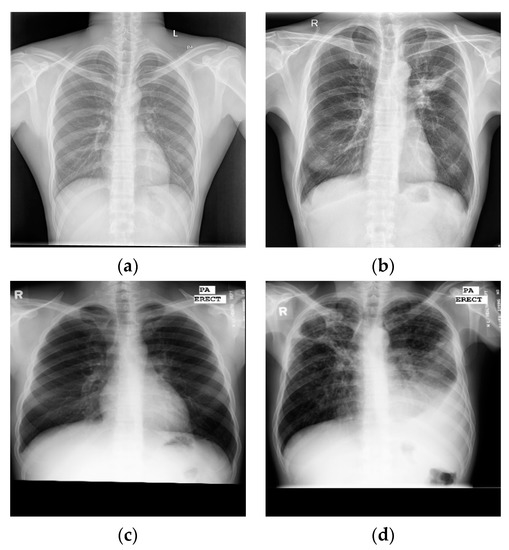

Here, this article uses the posterior anterior chest X-ray image datasets publicly released by the National Library of Medicine (NLM) [17]—the Montgomery and Shenzhen datasets—as shown in Figure 5, where the labels of each image are marked by experienced radiologists.

Figure 5.

Examples of chest X-ray images from CHN datasets: (a) normal chest X-ray; (b) tuberculosis chest X-ray. Examples of chest X-ray images from MC datasets: (c) normal chest X-ray; (d) tuberculosis chest X-ray.

(1) The Shenzhen, China dataset (CHN): The image format is PNG; the resolution of the images was variable but around 3000 × 3000 × 3 pixels, with 333 images of different TB patients and 329 images of normal controls (Figure 5a,b);

(2) The Montgomery dataset (MC): The image format is PNG; the resolution of the images was 4020 × 4892 × 3 or 4892 × 4020 × 3 pixels, with 58 images of different TB patients and 80 images of normal controls (Figure 5c,d).